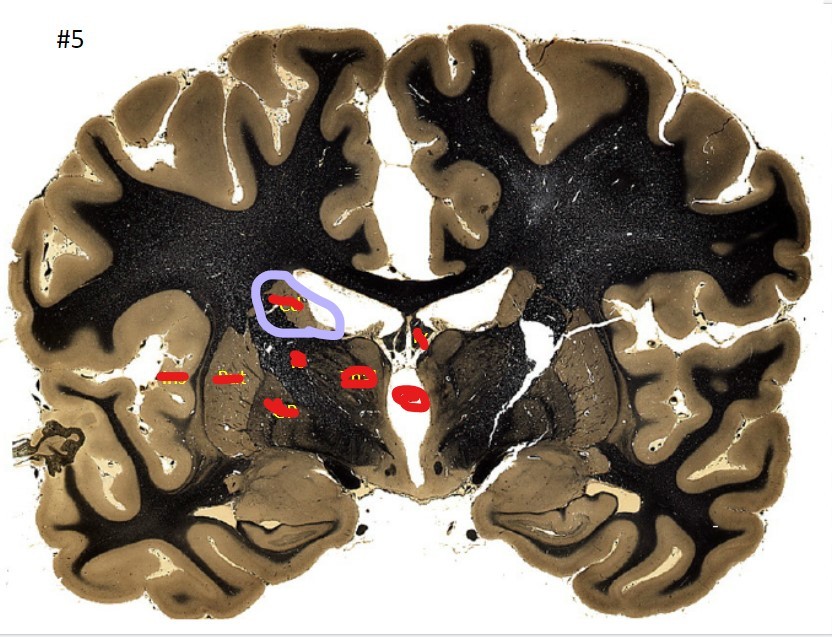

Q

what is the circled area (#5)?

A

the caudate nucleus

20

21

the 3rd ventricle

22

23

the globus pallidus

24

25

the internal capsule

26

the putamen

27

the amygdala

28

the beginning of the hippocampus